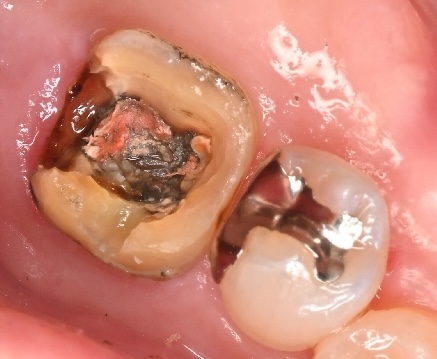

先日来院された患者様のケースです。右下の銀歯に違和感があるとのことで、金属を外してみることにしました。

銀歯を外すと、内部のセメントが劣化し、黒く大きなむし歯(二次カリエス)が広がっていました。 まずは、この感染した部分を大まかに取り除きます。